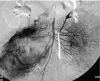

Gastrointestinal stromal tumours (GISTs) comprise a group of smooth muscle mesenchymal alimentary tract tumours of variable malignancy. Recently, the pathophysiology and radiology of these tumours has generated enormous interest following the discovery of a specific, highly effective, chemotherapeutic agent in the form of ST-571 (Imatinib; Glivec, Novartis, Frimley UK). At the time of this review, 106 patients with malignant gastrointestinal stromal tumours seen at the Royal Marsden Hospital have been entered into trials examining the efficacy of varying doses of Imatinib. Burkill et al., also from the Royal Marsden Hospital, have previously reported the distribution, imaging features and pattern of metastatic spread of these tumours (Burkill GJ, Badran M, Al-Muderis O et al. Malignant gastrointestinal stromal tumor: distribution, imaging features, and pattern of metastatic spread. Radiology 2003; 226: 527-32). This new review re-examines the radiological features of GISTs at presentation and well as their changed imaging features following treatment with Imatinib.